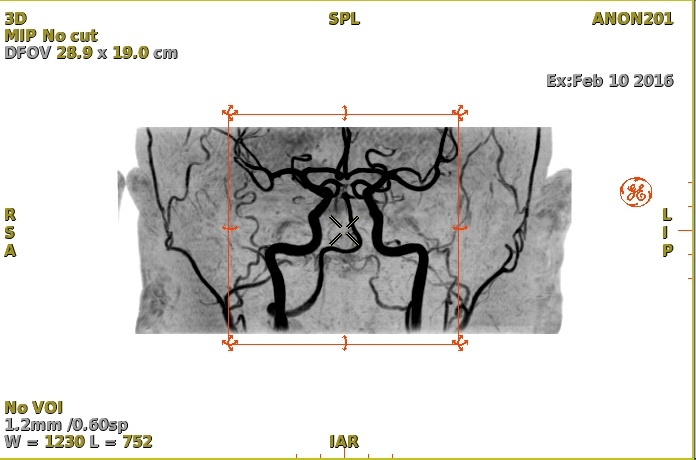

• Inverse Gray inverts the image gray scale.

Figure 3. Example of Inverse gray on a MIP image